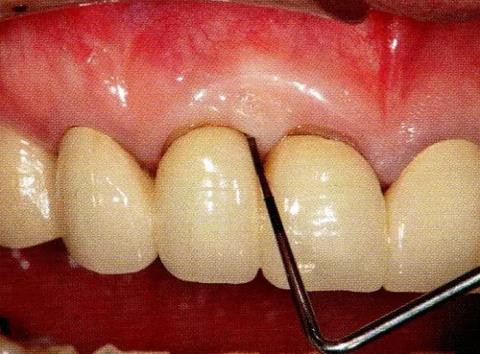

▼圖13-6 術(shù)后8個月的狀態(tài)。牙周探診值改善到4mm,牙齦萎縮基本沒有出現(xiàn)。進行GTR法時,上頜顎側(cè)牙齦容易出現(xiàn)壞死,但是使用EMD促生長因子處理時,不容易出現(xiàn)牙齦壞死和退縮。